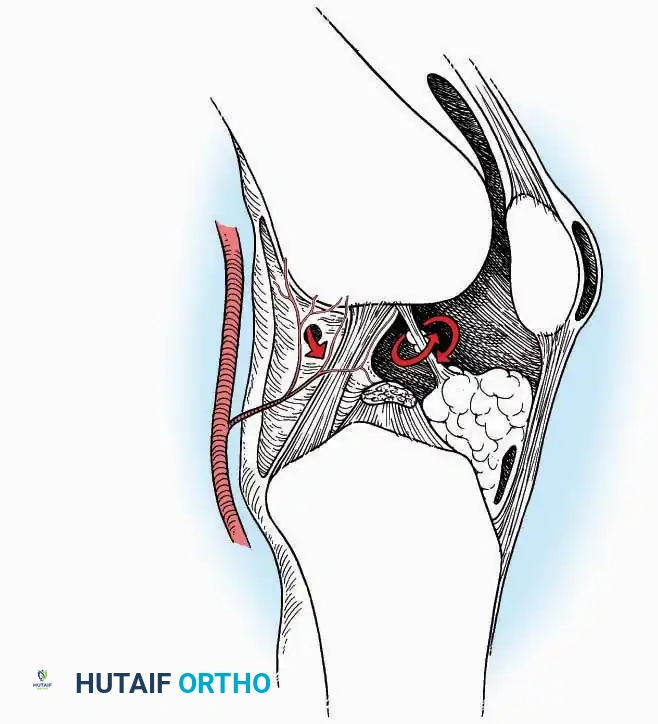

Anterior Approach

Indications: Total ankle arthroplasty (TAA), anterior ankle arthrodesis, and excision of anterior tibial/talar osteophytes (anterior impingement).

Surgical Technique:

* Incision: Make a 10 to 15 cm longitudinal incision over the anterior aspect of the ankle, centered exactly midway between the medial and lateral malleoli.

* Superficial Dissection: Incise the superficial fascia. Identify and protect the superficial peroneal nerve branches laterally and the saphenous nerve medially.

* Internervous Plane: The deep dissection exploits the plane between the Extensor Hallucis Longus (EHL) tendon (innervated by the deep peroneal nerve) and the Extensor Digitorum Longus (EDL) tendons (also innervated by the deep peroneal nerve).

* Neurovascular Bundle: Incise the extensor retinaculum. Carefully identify the anterior tibial artery and the deep peroneal nerve, which typically lie between the EHL and EDL, or directly deep to the EHL. Retract the neurovascular bundle laterally with the EDL, or medially with the EHL, depending on the specific anatomical variant encountered (lateral retraction is most common).

* Capsulotomy: Incise the anterior joint capsule longitudinally. Elevate the capsule subperiosteally from the anterior tibia and the talar neck to expose the entire tibiotalar articulation.